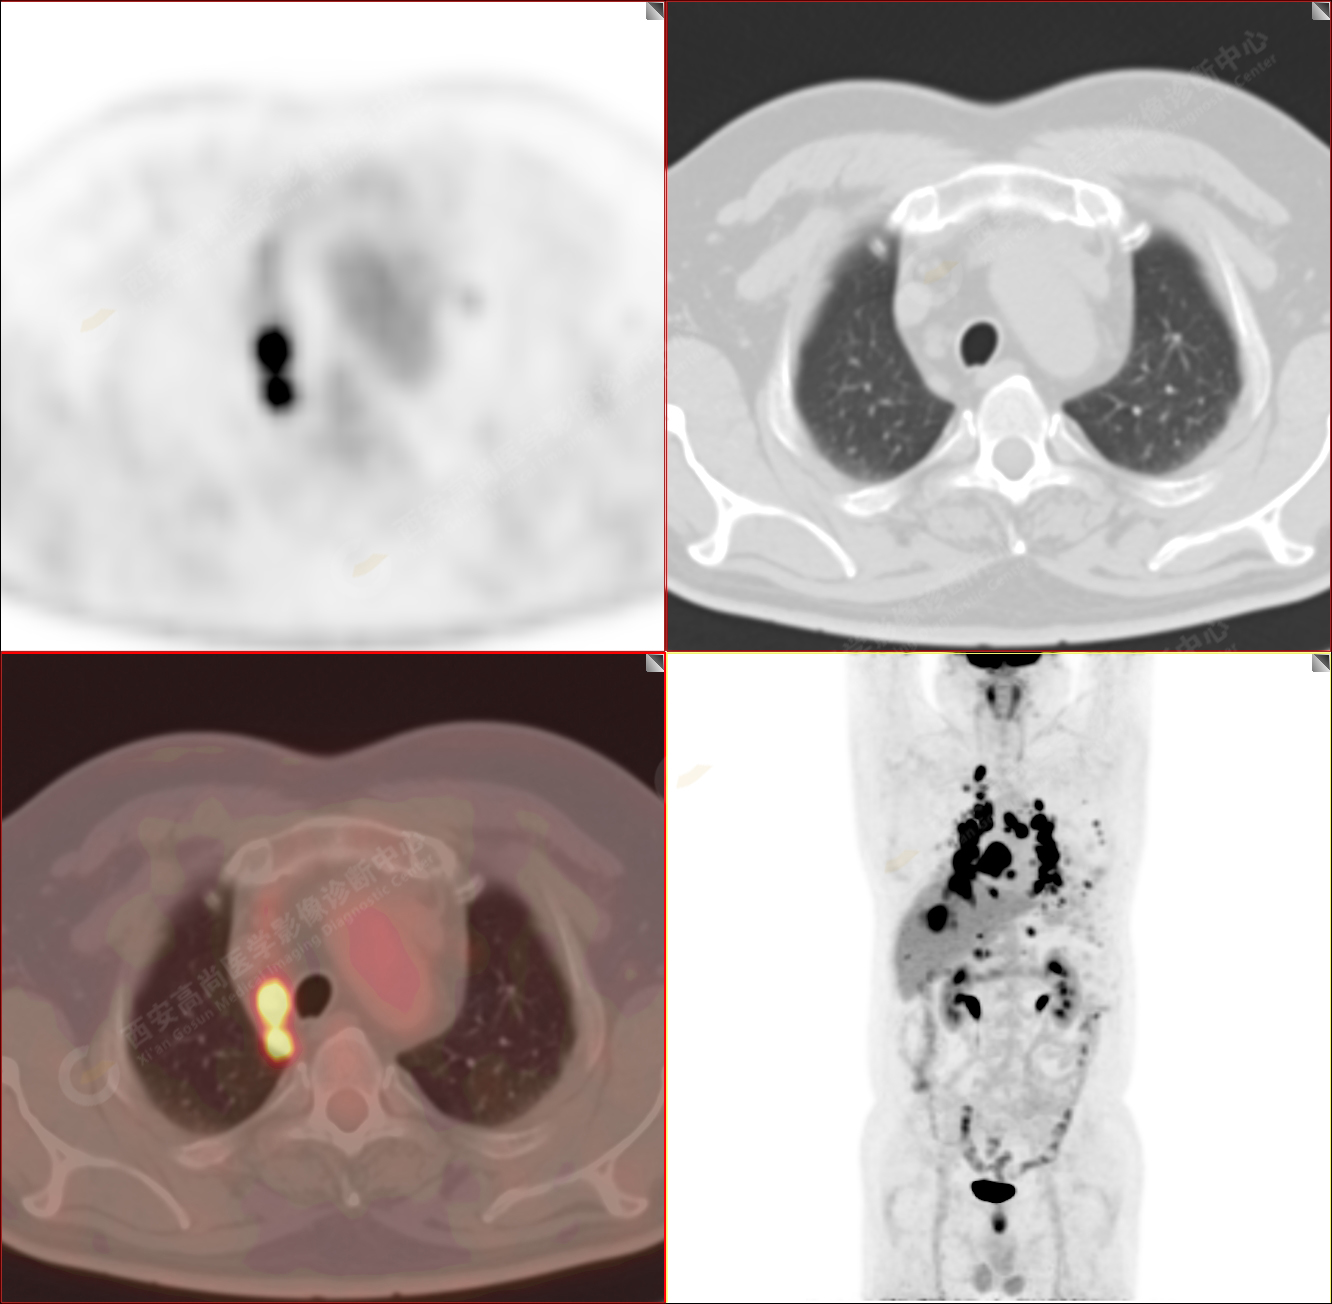

男性,53歲,頭暈半月入院,CT發(fā)現(xiàn)肺內(nèi)腫塊,雙肺多發(fā)大小不等實性及粟粒樣結(jié)節(jié),雙肺門及縱隔多發(fā)腫大淋巴結(jié)。病程中無發(fā)熱、胸悶氣及胸部不適。既往:左側(cè)肋骨外傷史。

PET/CT圖像